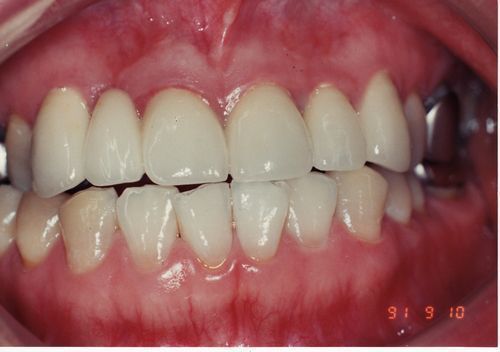

審美の意識の高まりと共に金属の詰め物を白い詰め物に置き換えたいと希望する患者さんも増えてきました。良い材質の出現で欠けやすい欠点もある程度カバーできるようになりました。下の写真は5番の小臼歯をハイブリッドセラミックスで修復後、6番7番の大臼歯の金属の詰め物を白いハイブリッドセラミックスで置き換えました。見た目がずいぶん変わりました。これで時代劇出演もOKです。ハイブリッドセラミックスは保険適用外になります。部分の詰め物の場合1本5万円です。

術前                       術後

8797術前.jpg

8797術後.jpg